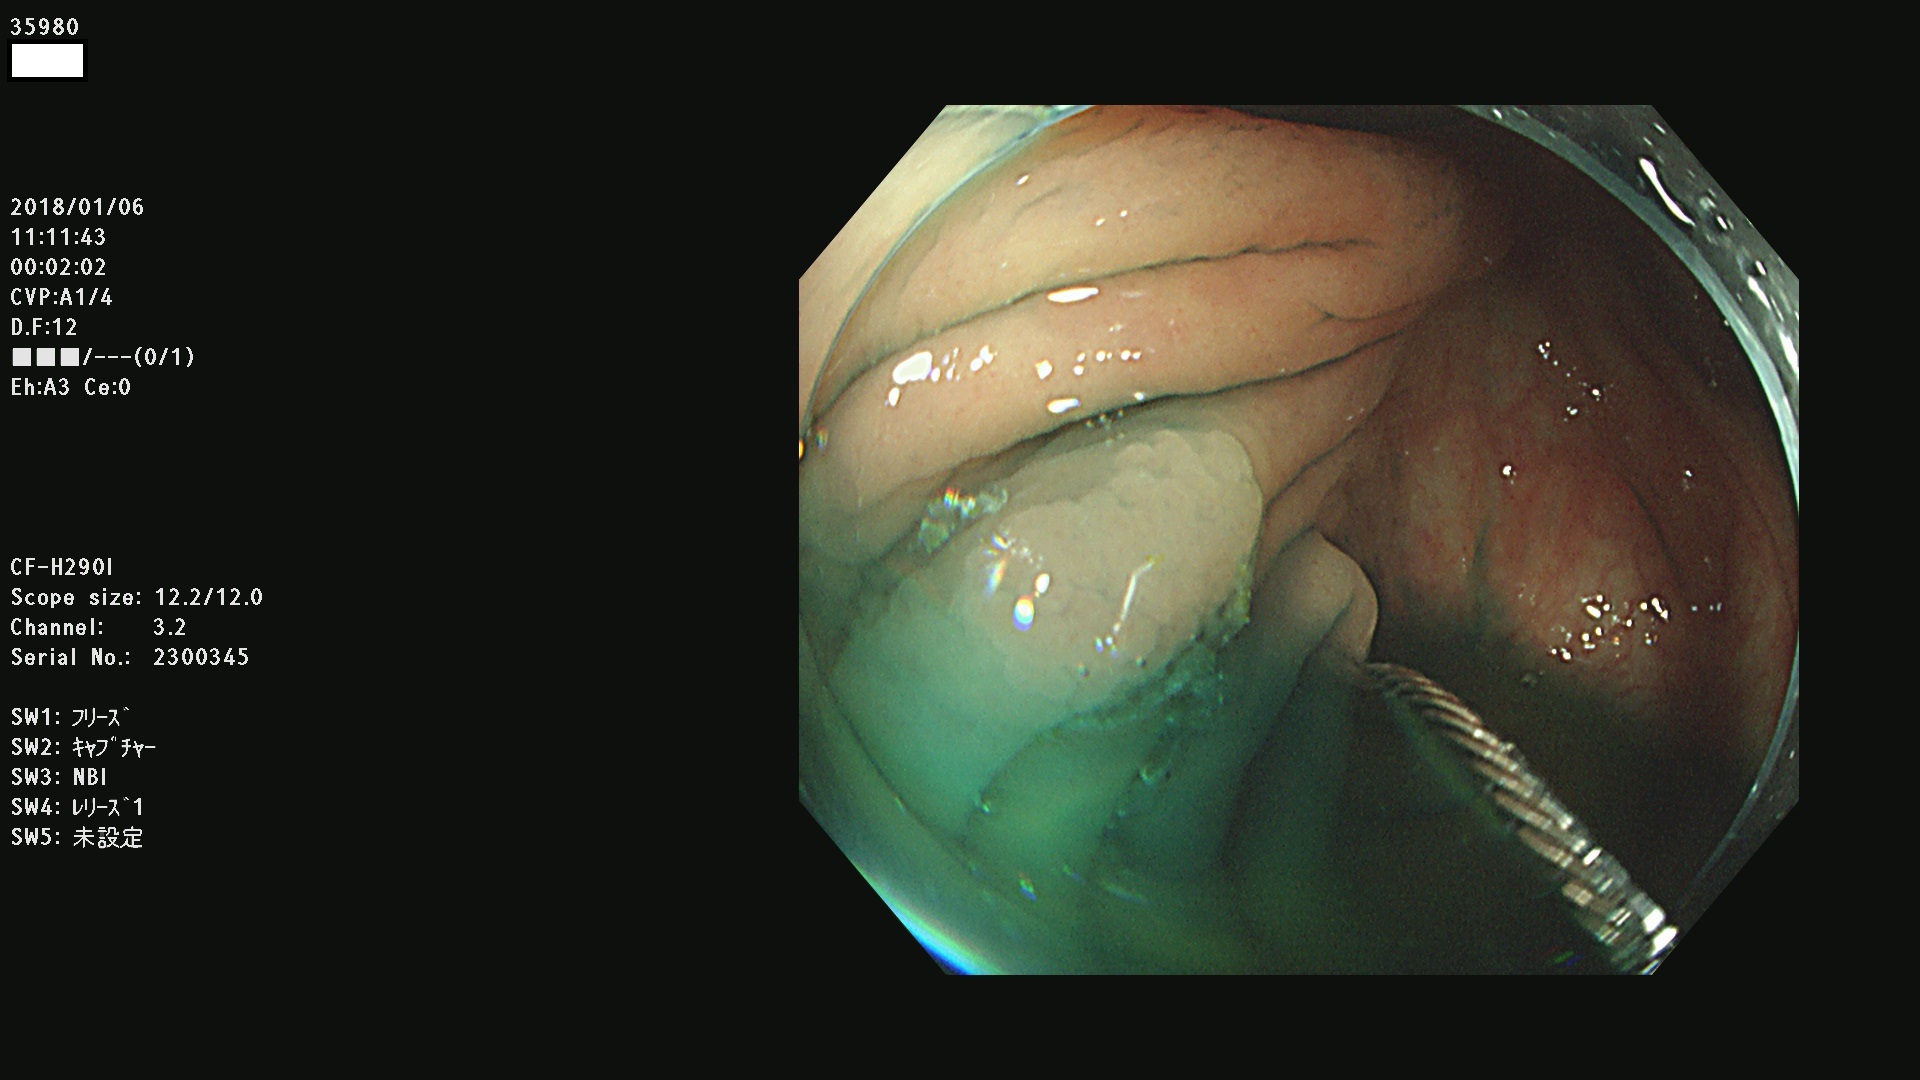

腺腫発見率43 % (カルテ番号 35900〜35999の100名の方の検査結果で集計)大腸癌検診最新情報

以下のカルテ番号の方に腺腫(Adenoma,Group3〜5)が見つかりました(集計法)

35900 35901 35904 35908 35912(SSA/Pのみ) 35914 35918 35922 35925 35926 35928 35931 35932 35933 35934 35937 35939 35943 35945 35947 35949 35951(SSA/Pのみ) 35952 35958 35959 35963 35964(SSA/Pのみ) 35965 35970 35972 35976(SSA/Pのみ) 35977 35978 35979(SSA/Pのみ) 35980(SSA/Pのみ) 35982 35983 35985 35991 35993 35995 35997 35999

発見困難で危険性の高い平坦型病変(上記100名より抽出) ![]()